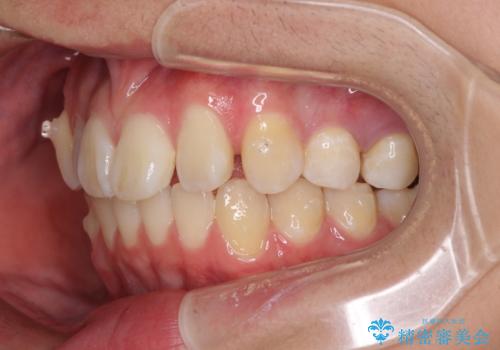

- 八重歯を気にして来院された高校生の患者様です。

ボディーコンタクトの激しい部活動を行っているため、補助装置とインビザラインを用いて、部活動を継続しながら治療を行うこととしました。

八重歯を効率よく改善するため、補助装置を使用して上顎の奥歯を後方に移動させました。

部活動をしながらでしたが、マウスピースをしっかりと装着してくださったので、1年半程度で終了することができました。